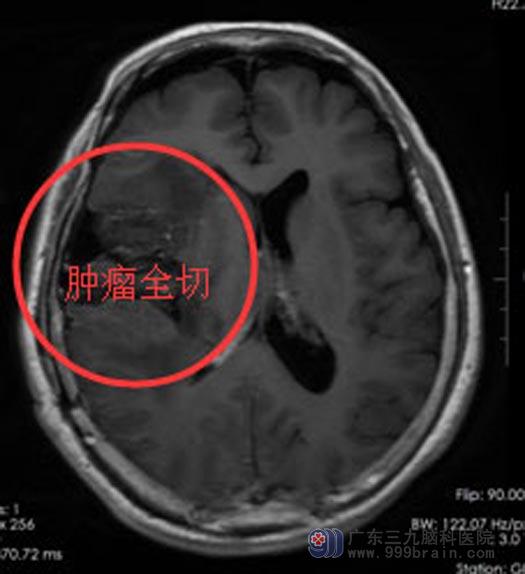

周阿姨和家属都同意手术治疗。由综合神经外科鲁明副院长主刀在唤醒麻醉下行“右额颞顶基底节占位切除术+硬脑膜修补术+颅骨成形术”。导航定位右额颞顶基底节区肿瘤组织,术中唤醒患者,电生理监测运动中枢,结合导航,避开上下肢运动区,显微镜下将肿瘤分块切除,手术非常顺利。

术后,周阿姨恢复很好,肢体肌力正常,言语及思维清晰。